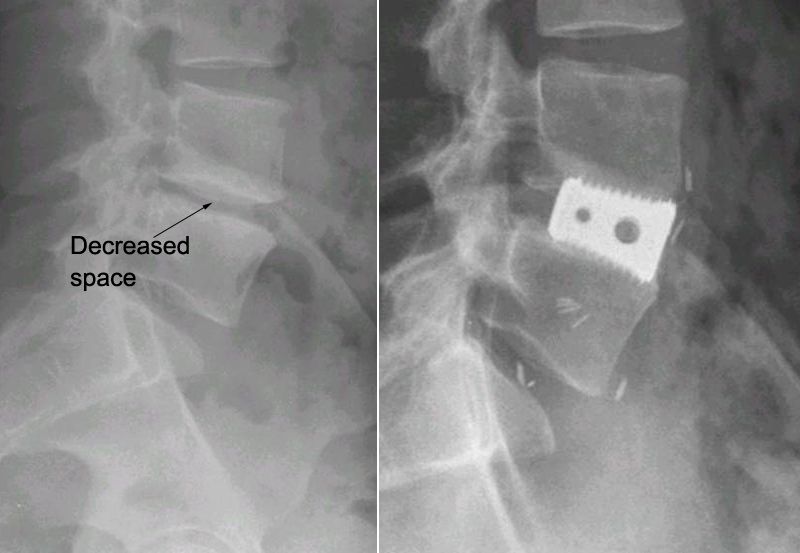

X-rays of decreased disk space and ALIF

(Left) This X-ray of the lumbar spine shows decreased disk space between the vertebrae. (Right) In an anterior lumbar interbody fusion (ALIF), a metallic interbody cage has been inserted to restore the normal height of the disk space. The bone graft is contained within the cage and cannot be seen on X-ray.